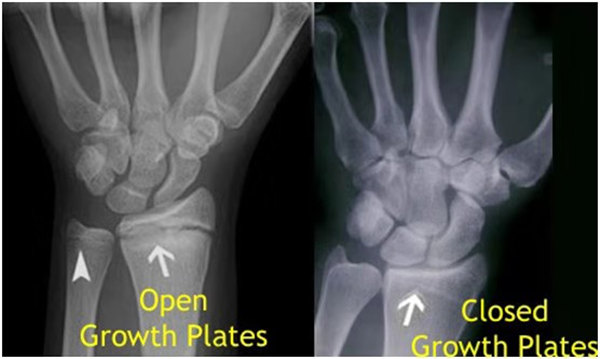

其實(shí)想要了解孩子的生長(zhǎng)發(fā)育情況或者說(shuō)孩子未來(lái)身高的趨勢(shì),測(cè)骨齡是個(gè)好辦法。臨床上通常拍攝兒童的左手正位X光片 , 采用《中華-05》骨齡標(biāo)準(zhǔn)對(duì)手腕骨發(fā)育程度進(jìn)行骨齡評(píng)價(jià)。

我們都知道,人體的高矮是由骨骼的生長(zhǎng)發(fā)育決定的,特別是下肢長(zhǎng)骨。長(zhǎng)骨呈長(zhǎng)管狀,在長(zhǎng)骨的兩端有一種專管骨骼生長(zhǎng)的骺軟骨,它與干骺端之間有一盤狀軟骨結(jié)構(gòu)稱為骺板(線),在幼兒的X光片上表現(xiàn)為一條較寬的透光帶。 (見(jiàn)下圖)

未成年時(shí)隨著年齡的增加骺軟骨端不斷骨化,骨骼就不斷增長(zhǎng)。當(dāng)骨骺線完全閉合時(shí)骨骼就停止生長(zhǎng),個(gè)子也就不再增長(zhǎng)了。一般骨骺端完全閉合的年齡是18~20歲左右。